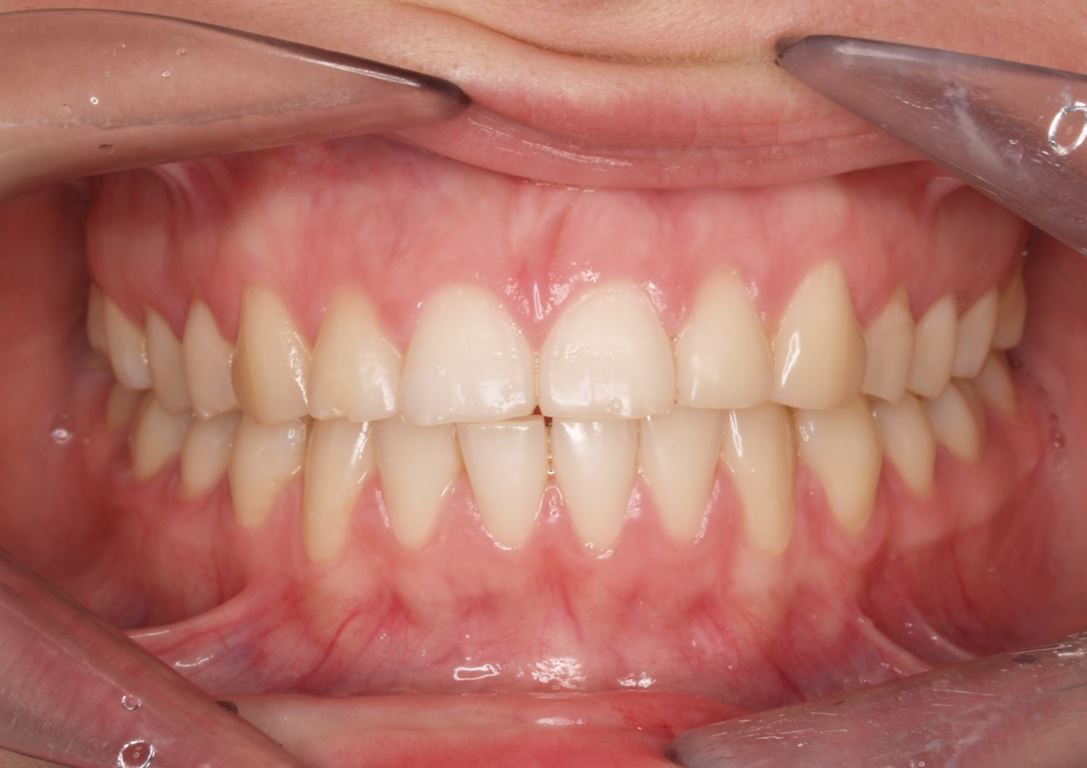

W badaniu klinicznym stwierdzono uogólnione starcie wszystkich zębów z ekspozycją zębiny, nieprawidłowe proporcje zębów przednich, liczne odpryski szkliwa na brzegach siecznych i relację tête à tête przednich zębów. W podstawowym badaniu klinicznym stwierdzono zwiększone napięcie mięśniowe bez objawów bólowych, prawidłową ruchomość oraz brak objawów patologicznych ze strony stawów skroniowo-żuchwowych.

W pierwszym etapie diagnostycznym wykonano zdjęcia zewnątrz- i wewnątrzustne (ryc. 1-12).

Wykonano także modele diagnostyczne zaartykulowane w relacji centralnej (RC), którą zarejestrowano ze względu na zwiększone napięcie mięśniowe z wykorzystaniem deprogramatora Koisa (ryc. 13-15), oraz zdjęcie pantomograficzne (ryc. 16) i cefalometryczne. Analiza modeli w RC wykazała przesunięcie żuchwy w kierunku doprzednim w stosunku do pozycji maksymalnego zaguzkowania i przedwczesne kontakty funkcjonalne na zębach bocznych, co tłumaczyło obecność odprysków szkliwa na brzegach siecznych górnych zębów (szczególnie wyraźne na zębie 12) (ryc. 14, 17). Na modelach wykonano studium funkcjonalne mające na celu określenie, w jaki sposób można odtworzyć prawidłową funkcję, tzn. uzyskać prawidłowy nagryz pionowy i poziomy oraz prowadzenie przednie (ryc. 18-20).